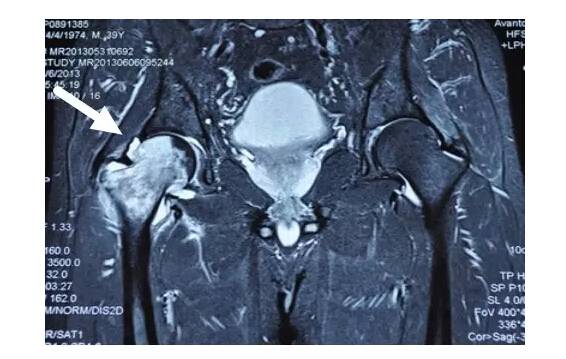

I期病人有髋部症状,X线片正常,磁共振出现异常

I期的患者在口服以上药物的同时,可以行股骨头坏死钻孔减压术,并且要定期复查,密切观察病情发展,尽量避免重体力劳动和爬山爬楼。